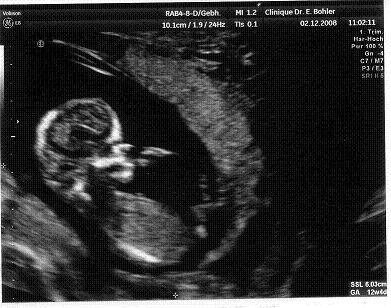

Indulás a munkaügyi felügyelethez, ahol egy nagyon készséges, kedves, megértő úriember minden tőle telhetőt megtett, h engem a lehető legpontosabban tájékoztasson a jogaimról. A legdurvább az volt, amikor ez a mondat hagyta el a száját: "azért, mert maga terhes, még nem kötelezhető a munkáltatója, h tovább működtesse az irodát, ha egyszer úgy döntött, h bezár. Mégis mit vár?"

A megoldás az előző munkahelyem munkaügyisétől származik, megyek táppénre, már a jövő héttől. Igazából arra lettem volna csak kíváncsi amúgy, h ha dolgozom dec. 31-ig (egyrészt a pénz miatt, meg hogy a kolléganőm ne szívjon akkorát), utána is ugyanúgy elmehetek-e tp-re, de azt mondták, h kiskapuk mindig vannak, menjek most, az a biztos.